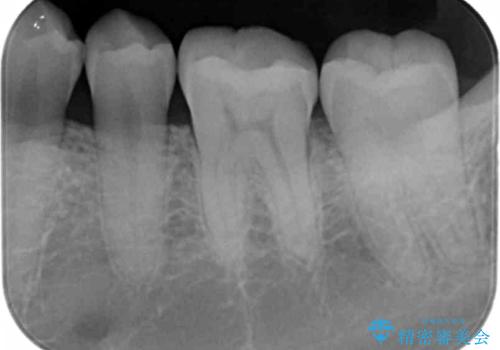

奥歯が欠けた セラミックインレーでの治療

- 奥歯が欠けたとのことで来院されました。

白い詰め物をご希望されたため、セラミックインレーでの治療を行います。

治療前後で比べると、詰め物と歯の間のすき間もなくなりセラミックインレーの適合の良さが伺えます。